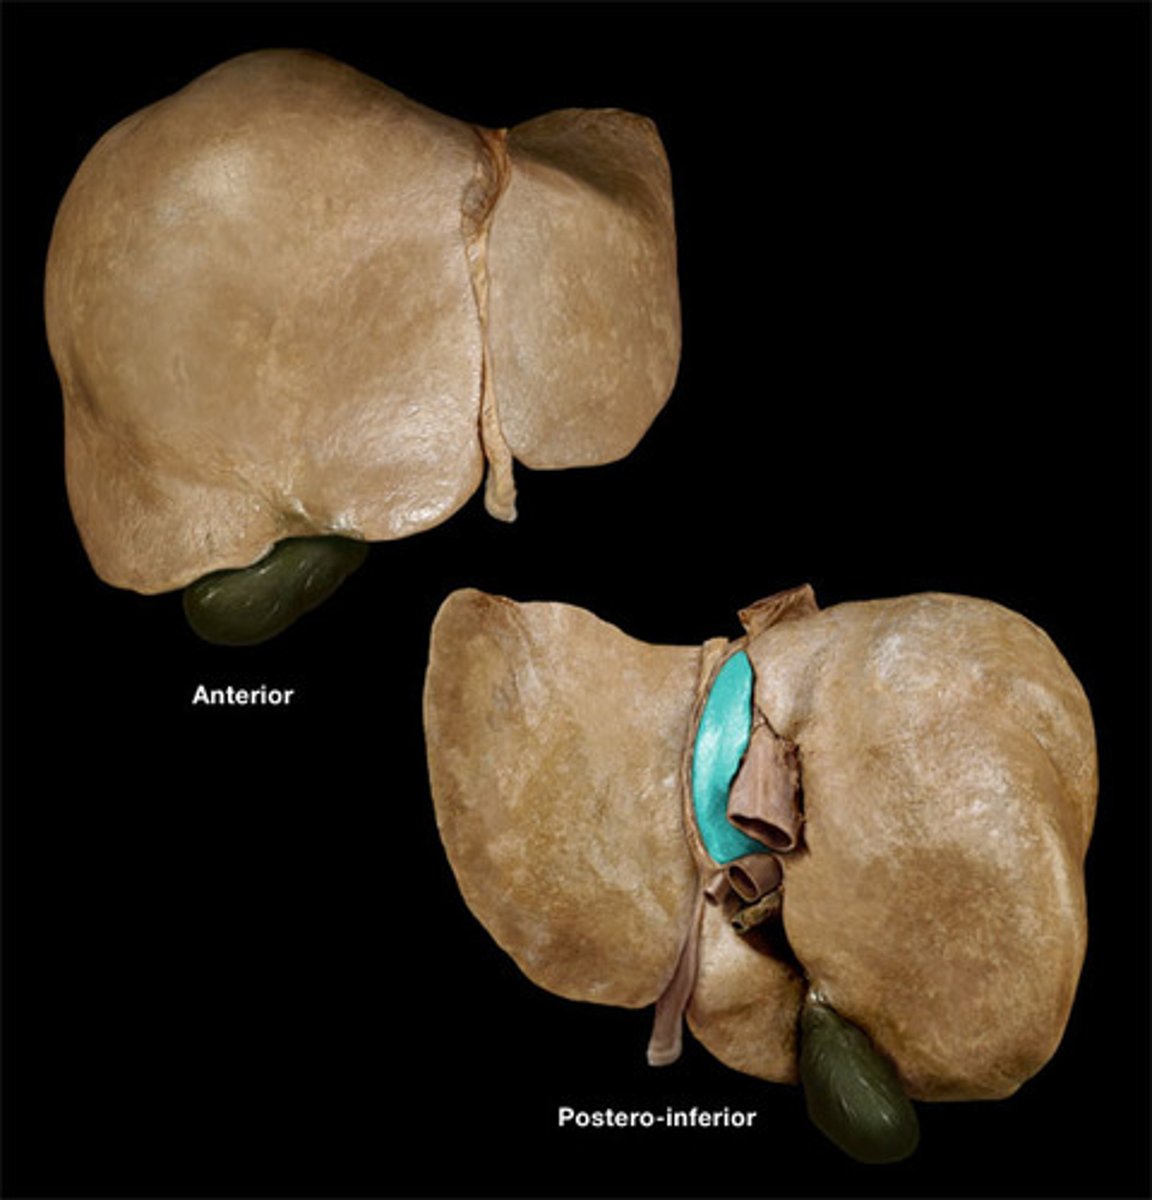

round ligament of liver

remnant of umbilical vein

porta hepatis

where the blood and lymph vessels, bile ducts, and nerves enter and leave the liver